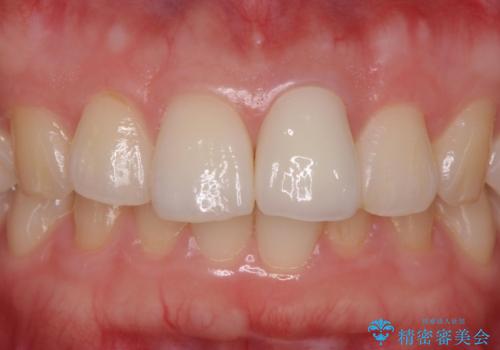

ガタつきと変色の両方を改善することができ、大変喜んでいただけました。

少しのガタつきであれば、矯正治療を行わなくても改善できる場合があります。